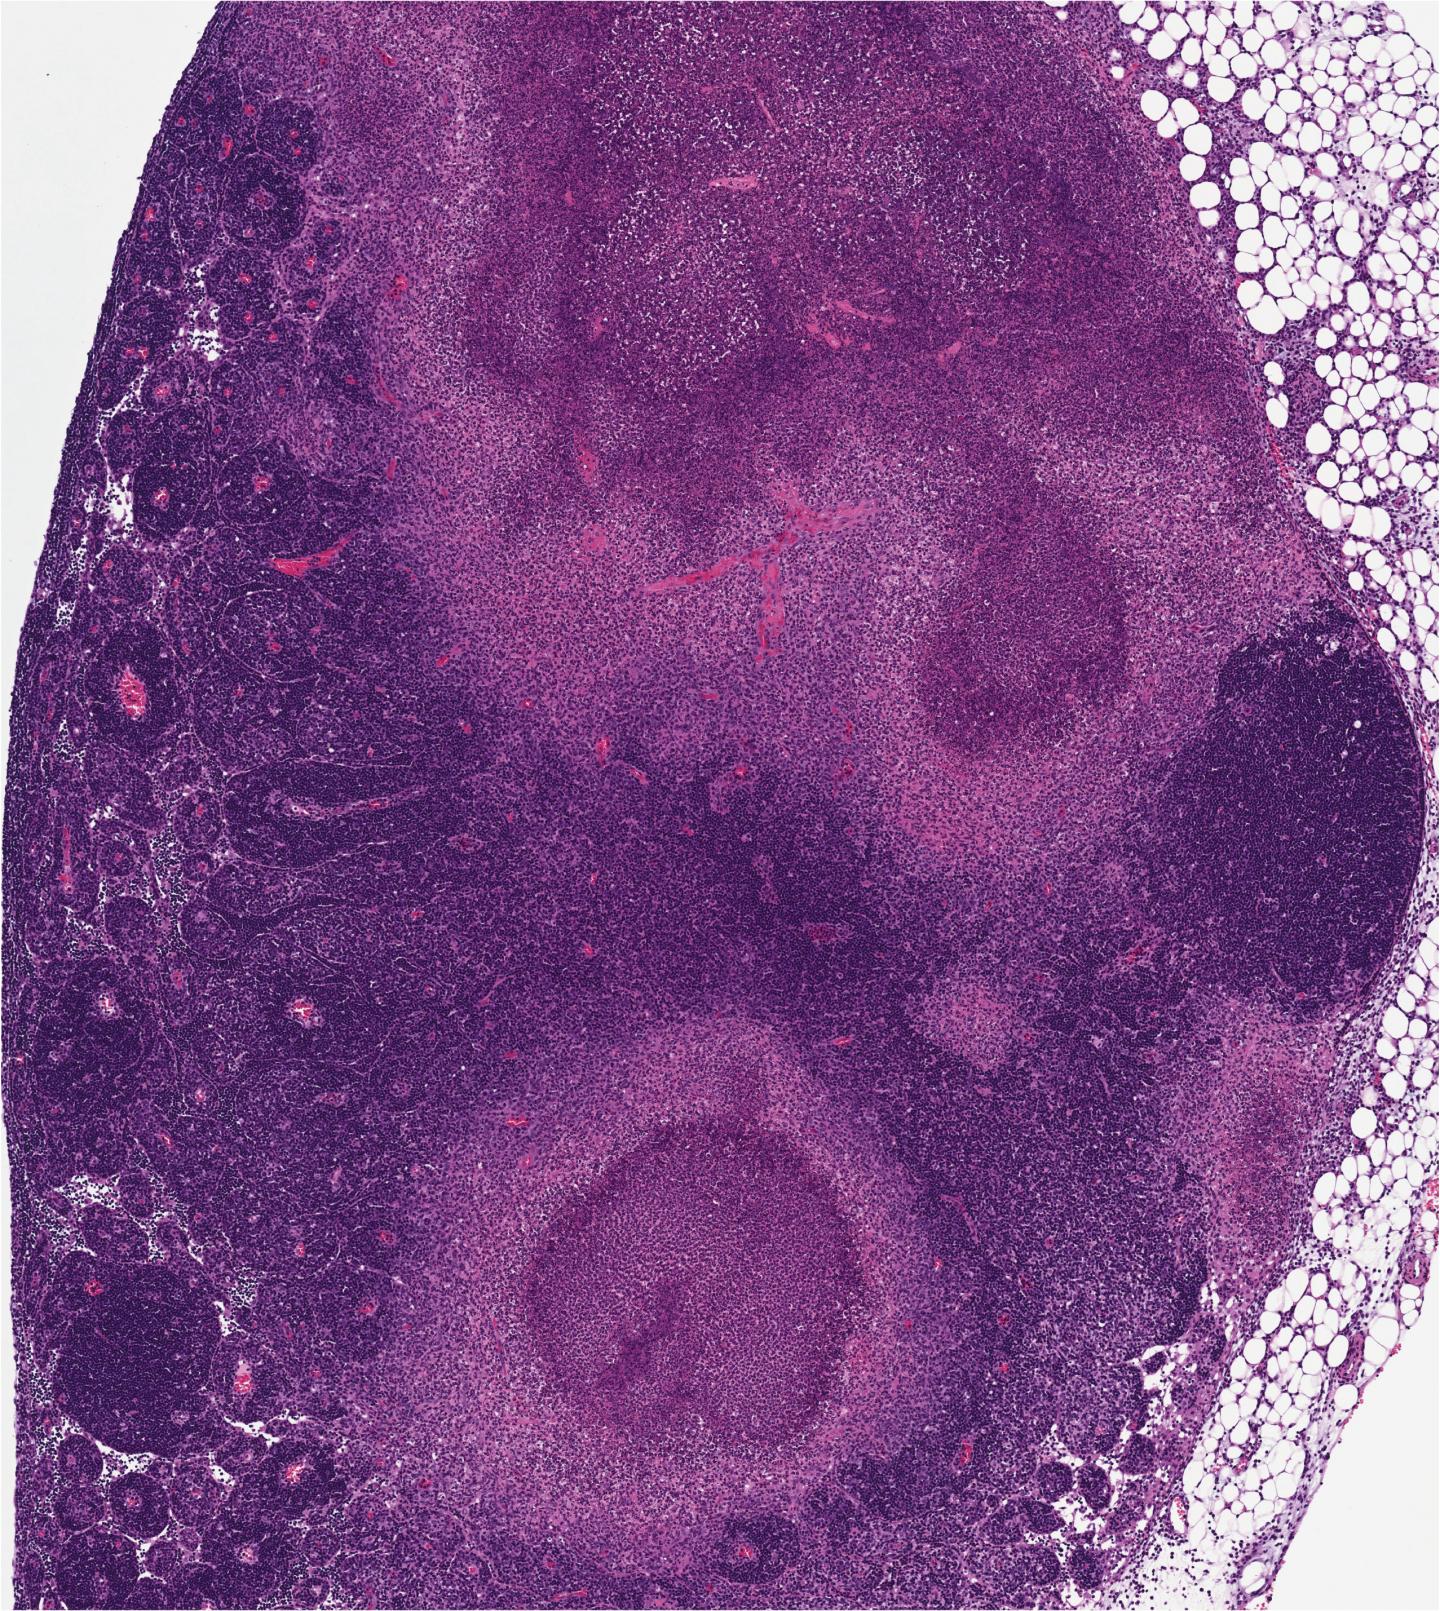

Imunitný systém ustavične monitoruje všetky kúty nášho tela a pátra po cudzích organizmoch, ktoré by nám mohli uškodiť. Patogény si však vytvorili viacero stratégií, ktorými sa tomuto pátraniu dokážu vyhnúť, napríklad sekréciu proteínov zabraňujúcich telu vytvoriť imunitnú odozvu. Igor E. Brodsky z Pennsylvánskej univerzity a jeho tím nedávno identifikovali náhradný alarm vnútri buniek, ktorý sa aktivuje, keď sa patogén pokúsi rozvrátiť imunitný systém.

Umierajúce nakazené bunky totiž komunikujú so zdravými bunkami, pričom svojou obeťou dajú susedom šancu, aby sa zachránili aspoň ony. Tento novoobjavený mechanizmus by mohol vysvetliť, ako je možné, že imunitný organizmus dokáže reagovať aj na hrozby, ktoré sú špeciálne uspôsobené na to, aby akúkoľvek reakciu znemožnili. Náhradný alarm by sa, okrem iného, mohol dať v budúcnosti využiť na zabíjanie nádorových buniek tým, že tieto bunky presvedčia, že všetko je stratené a treba chrániť aspoň svojich susedov.